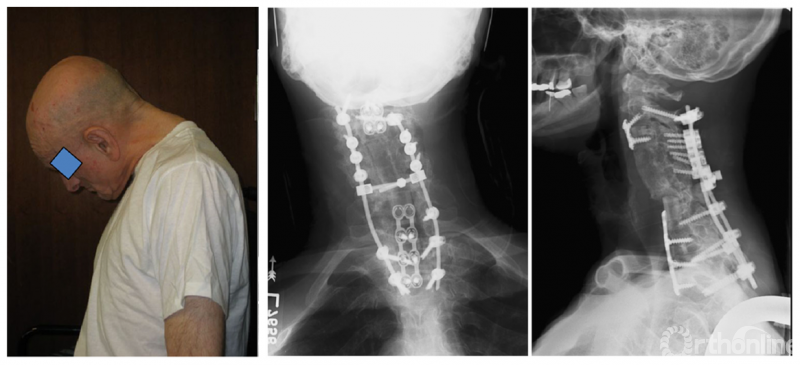

颈椎截骨是治疗颈胸段后凸畸形的有效技术,其适应证:包括重度颈胸段后凸畸形致平视功能受限、脊柱后凸畸形经胸腰椎截骨术后平视功能仍受限及颈胸段近端交界性后凸畸形需再次手术。

单纯颈胸段和胸腰段后凸畸形可分别行颈胸段、胸腰段截骨矫正,整体后凸畸形则要考虑截骨顺序。Koller 等认为若患者有重度颈椎及轻中度胸腰椎后凸畸形可先行颈椎截骨术,术后根据患者特点决定是否行进一步腰椎截骨。Kim等认为在患者脊柱极重度后凸畸形(chin-on-pubis )时,可按颈椎、胸椎和腰椎顺序依次截骨。